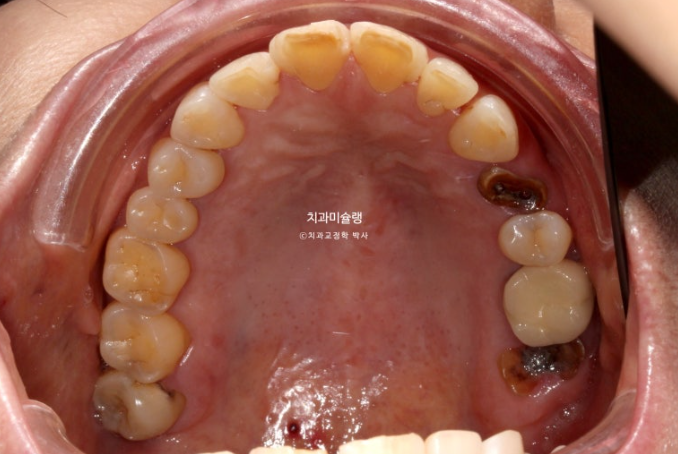

레진이 차지하는 비중이 컸습니다

아래 앞니 사이사이는 공간이 없는 데 위 앞니 사이사이에만 큰 공간이 있다면

이 공간을 교정으로 100% 메꿀 수 없습니다.

최대한 공간을 줄여놓고 남은 미세공간은 레진으로 마무리 해야 합니다.

인비절라인 라이트 치료 권유드렸습니다.

아래 앞니는 원래 있던 블랙트라이앵글을 없앨 겸 치간삭제를 동반하기로 합니다.

또한 아래 앞니가 위 앞니를 밀어내어 위 앞니 벌어짐이 심해지지 않도록 아래 앞니는 함입도 필요합니다.